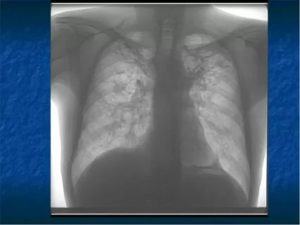

Флюорография лёгких определяет состояние органов грудной клетки, сосудов и сердца. На флюорографических снимках можно увидеть легочные заболевания, новообразования и воспалительные процессы.

Исследование лёгких позволяет вовремя обнаружить патологические изменения лёгочных тканей и может показать признаки сердечной недостаточности. Флюорограмма показывает внутренние органы в грудной области, их соединения. Рентгеновские лучи проходят сквозь тело человека и переносят на плёнку рисунок внутренних органов.

С помощью флюорографии легких можно удается выявить следующие заболевания:

• пневмонию;

• злокачественную опухоль;

• склероз;

• скелетно-мышечные отклонения;

• фиброз;

• сердечно-сосудистые болезни (увеличение, смещение сердца);

• грыжу;

• туберкулёз;

• кисты;

• абсцессы.

Также флюорография поможет обнаружить инородные предметы в лёгких или дыхательных путях.

Полученное при помощи флюорографического аппарата изображение ОГК (органов грудной клетки) может дать исчерпывающие ответы о состоянии пациента или стать причиной назначения уточняющей диагностики, если есть на то основания. Даже на небольшом флюорографическом кадре для рентгенолога видны характерные следы, говорящие о том или ином заболевании.